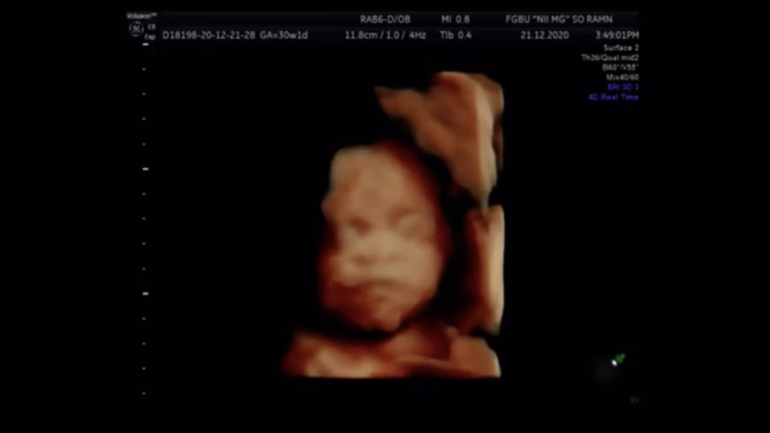

Наш «безносый» 3 скрининг. Фото

Ну что, прошли мы третий скрининг.

В 25 недель по прежнему не видели нос.

Но наш малыш вырос!

Даже опережает на 1 день теперь 😂

Вес 1,5кг

Нос вогнут, но он есть😅

Лежал, зевал🙏🏼

Ну и наши фото))